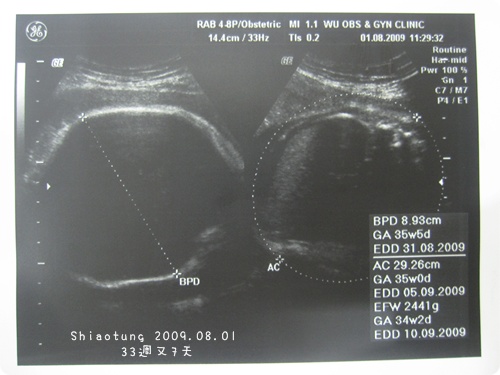

頭圍BPD約:8.93cm→左邊

體重AC約:2441g→右邊

雖然都是標準內,

但是明顯就是有大一點,

因為預產期上面標示都有提前...